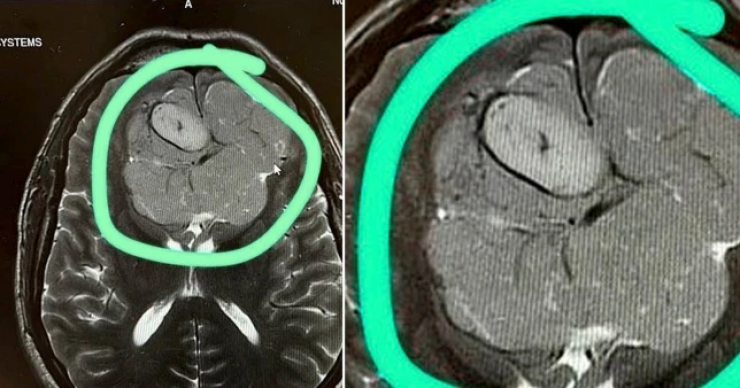

На следующий день специалисты с помощью МРТ выяснили, что зрение у мужчины упало из-за большой опухоли. Новообразование давило на мозг.

Уже через неделю мужчину положили в больницу. В конце лета 2022 года врачи провели операцию по удалению опухоли, которая длилась 14 часов.